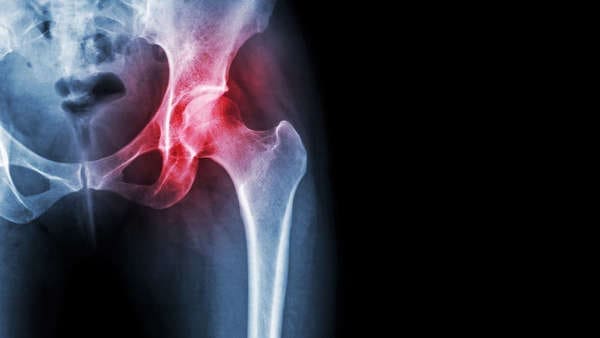

Causes de la douleur à la hanche droite

Causes physiques

Arthrose Détérioration du cartilage dans l’articulation de la hanche.

Tendinite Inflammation des tendons, souvent suite à des efforts prolongés.

Bursite Inflammation des bourses séreuses affectant l’amplitude du mouvement.

Fissures osseuses Fractures pouvant survenir après un choc ou une chute.